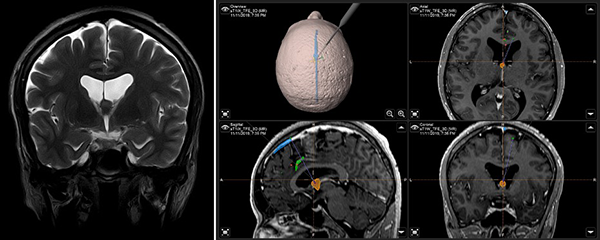

Paciente masculino de 40 años, sin antecedentes patológicos, atendido en nuestra institución por presentar cuadro de 2 años de evolución caracterizado por cefalea holocraneana de moderada intensidad, intermitente. Dos meses previo a la consulta inicial había presentado pérdida de consciencia más un episodio de crisis convulsiva tónico-clónico generalizada. Al examen físico el paciente no presentaba deterioro del sensorio ni déficit neurológico evidente. El resto del examen no mostraba hallazgos relevantes. La resonancia magnética (IRM) evidenció una lesión ovoidea que ocupaba el foramen de Monro, isointensa respecto al parénquima cerebral en las secuencias T1 y T2, de 12x9x9 mm, su margen rostral y dorsal en contacto con el pilar anterior y cuerpo del fornix, respectivamente; con tenue realce a la administración del contraste. En la secuencia de tensor de difusión los diferentes tractos se aprecian con trayecto normal y adecuada disposición de las fibras. Sistema ventricular sin dilatación ni compresiones. Se realizó la exéresis total de la lesión a través de un abordaje interhemisférico transcalloso anterior guiado por sistema de neuronavegación (Figura 1). El curso postoperatorio transcurrió con una hemiparesia braquio-crural derecha transitoria, que cede en días subsecuentes con recuperación total de la fuerza muscular. El paciente fue dado de alta sin déficit neurológico agregado. El examen patológico reportó un quiste coloide. La IRM postoperatoria confirmó la extirpación total de la lesión con cambios postquirúrgicos asociados a craneotomía fronto-parietal derecha (Figura 2). El paciente se encuentra asintomático en seguimiento por la consulta externa.

Figura 1. (A) IRM T2W coronal: ubicación anatómica de la lesión en foramen interventricular; (B) IRM integrada al sistema de neuronavegación, planeación de abordaje quirúrgico.

Figura 2. (A) IRM T2W sagital postoperatoria muestra la ruta de aproximación y longitud de la callosotomía; (B) Imagen de pieza quirúrgica mostrando su exéresis total.